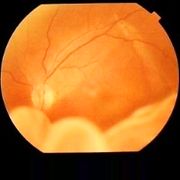

- 糖尿病视网膜病变是糖尿病的常见并发症,也是四大致盲眼病之一,其发病率和致盲率呈逐年上升趋势。的发生和进展与多种因素有关,早期诊断并积极治疗以防止或延缓其进展至关重要。对病人进行有计划、有目的的健康教育,帮助人们掌握卫生保健知识,促使人们树立

- 糖尿病视网膜病变糖尿病视网膜病变是什么意思糖尿病性视网膜病变属于糖尿病的严重并发症的一种,是糖尿病性微血管病变中最重要的表现,是一种具有特异性改变的眼底病变,根据是否出现视网膜新生血管为标志,将没有视网膜新生血管形成的糖尿病性视网膜病变称为